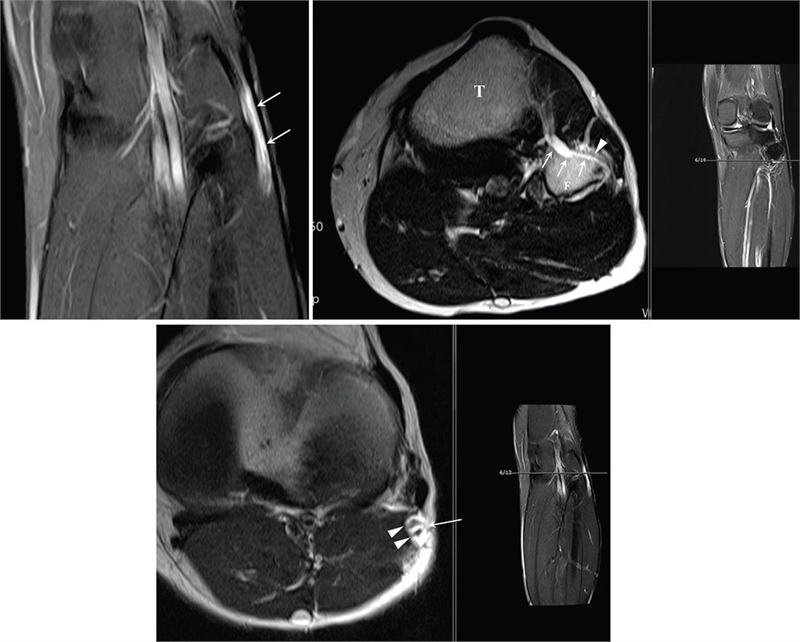

이번 성과는 지난 2018년 국제 학술지 ‘Asian Journal of Neurosurgery’에 발표한 손 교수의 증례 보고인 ‘비골신경 마비를 유발하는 신경곁조직 아래막 결절종’ 에서부터 시작되었다. 당시 손 교수는 2016년 메이요 클리닉 연구팀이 최초 확인하여 학계에 보고한 ‘신경곁조직 아래막(subparaneurial)’ 결절종이라는 매우 희귀한 변이를 실제 임상 현장에서 발견하고, 이를 성공적으로 치료한 과정을 상세히 기술하였다. 이는 기존에 알려진 신경외막(epineurium) 내부의 결절종과는 달리, 신경을 감싸는 더 깊은 층인 신경곁조직 아래 공간을 따라 낭종이 확산되는 독특한 병태생리를 규명한 중요한 전환점이 되었다.

특히 손 교수는 해당 연구를 통해 신경곁조직 아래막 결절종이 일반적인 결절종보다 신경 섬유에 더 밀착되어 있으며, 신경 줄기를 따라 매우 광범위하고 빠르게 전이될 수 있다는 사실을 확인하였다. 이러한 특성 때문에 일반적인 낭종 제거술로는 완치가 어려운 만큼, 관절과 연결된 신경 분지를 근본적으로 차단하는 정교한 수술 기법 적용이 필요할 수 있음을 제시하였다.